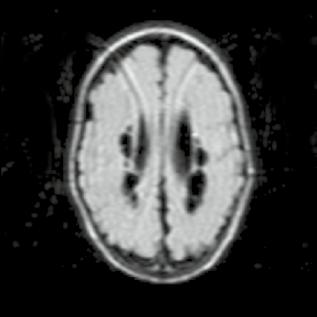

Kazuistika

Chlapec 2,5 měsíce starý, nedonošený, porodní váha 1440,0 g.

Obr. A4.1–A4.4 Periventrikulární leukomalacie – redukce bílé hmoty mozkové (šipka), periventrikulární pseudocysty, hypotrofie corpus callosum